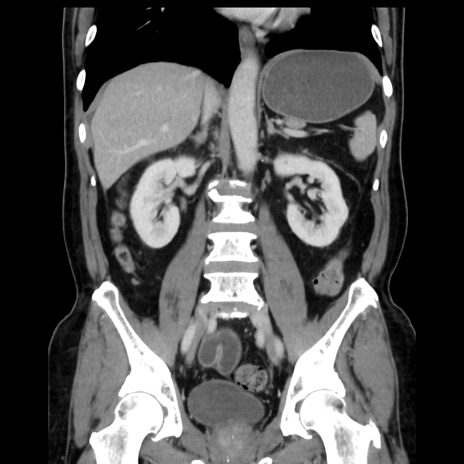

症例16(冠状断像)

【症例】 70歳代男性

【主訴】 腹痛、嘔吐

【現病歴】 約1ヶ月前より間欠的に腹痛と嘔吐あり、当院消化器内科を受診したところCTで多発する肝臓のLDAを指摘され、精査中であった。以降は消化器症状は安定していたが、2日前より嘔気と腹痛があり、同日より排便・排ガスが消失した。改善認めず、 本日、救急外来を受診した。

【既往歴】 大腸ポリープ切除後。

【身体所見】意識清明・会話良好、BT 36.3℃、BP 127/80mmHg、 P 80bpm、腹部:膨満あり、平坦・軟、上腹部正中および下腹部正中に圧痛あり、反跳痛なし、筋性防御なし。

【データ】WBC 7200、CRP 0.77